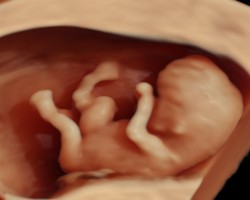

Ultraschalldiagnostik 12-14. SSW Erst-Trimesterscreening (NT-Mesung):

Das Ersttrimesterscreening ist eine differenzierte Ultraschalldiagnostik in der 12-14 SSW die ein ausführliches Organscreening und die Erfassung von sonografischen Chromosomenmarken, sowie eine Risikoberechnung aus Laborparamentern und Ultraschallmarkern beinhaltet. Diese Untersuchung ist keine Leistung der Krankenkassen und kann nur als IGEL-Leistung wahrgenommen werden

Mit Hilfe des Ersttrimesterscreenings (ETS) ist schon in der 12.-14. SSW durch die Beurteilung der Nackenfalte , des Nasenbeins und weiterer sonographischer Parameter (Ductus venosus, Trikuspidalklappe am Herzen etc.) sowie einer Blutentnahme (PAPP-A und freies ß HCG= plazentare Hormone) eine Risikoanalyse für das wahrscheinliche Auftreten einer Chromosomenstörungen Trisomie 21, Trisomie 13 oder Trisomie18 möglich. Die Erkennungsrate der Untersuchung beträgt ca.90-95% mit einer Falsch-Positiv-Rate von 2,5-5%.

Aufgrund des zusätzlichen ausführlichen Organscreenings können außerdem mit dieser Untersuchung Hinweise auf schwere organische Fehlbildungen frühzeitig erfasst werden. Nach Eingang der Laboruntersuchung wird eine für Ihre Schwangerschaft individuelle Risikoanalyse durchgeführt- das Ergebnis und damit das weitere Vorgehen entsprechend der Befunde wird mit Ihnen detailliert besprochen.

ETS- Bildergalerie